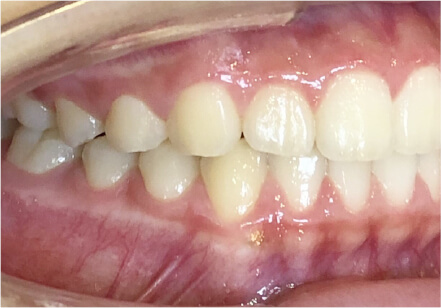

叢生の症例

11歳

女性

相談内容

上の前歯の歯並びが気になる(マイオスマイルからの移行)

カウンセリング・診断結果

インビザライン、拡大入れながらスペースを作成、下Eは出てきたら削りながら進める

治療内容・方法

全額アライナー矯正 クリアコレクト

術後の経過・現在の様子

クリアライナー使用

治療のリスク

痛み・歯根吸収・歯肉退縮・虫歯・後戻り

費用・治療期間

移行料金220,000円、月々16,500円、1年1ヶ月+myo2年3ヶ月